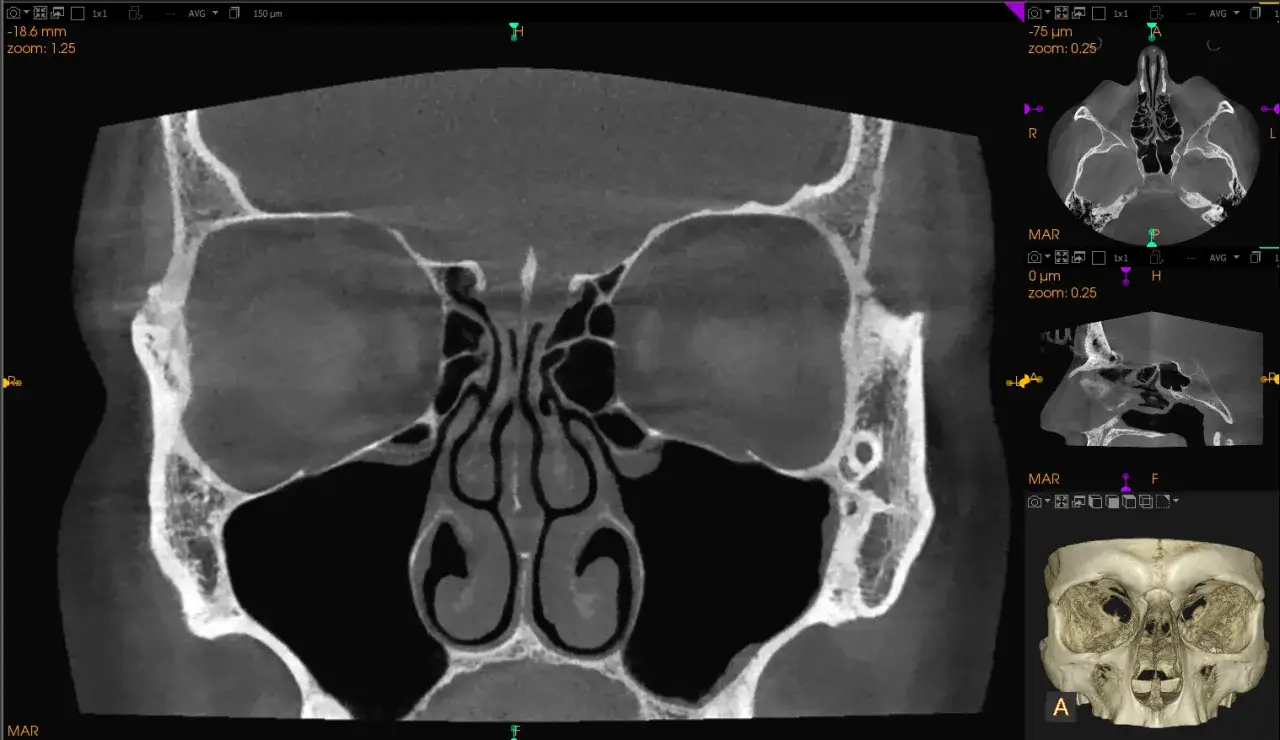

- Diagnostyka jest trudna i wymaga specjalistycznych badań obrazowych, jak TK lub MRI.

Dlaczego TK i MRI są kluczowe w potwierdzeniu diagnozy?

W przypadku podejrzenia zapalenia zatoki klinowej, badania obrazowe są absolutnie kluczowe i niezastąpione. Standardowe zdjęcie rentgenowskie (RTG) zatok jest w tym przypadku mało przydatne, ponieważ struktury kostne czaszki nakładają się na zatokę klinową, uniemożliwiając jej dokładną ocenę. Natomiast tomografia komputerowa (TK) i rezonans magnetyczny (MRI) pozwalają na precyzyjne zobrazowanie zatoki, ocenę stopnia jej wypełnienia wydzieliną, pogrubienia błony śluzowej, a także wykrycie ewentualnych powikłań w sąsiednich strukturach. MRI jest szczególnie cenne w ocenie tkanek miękkich i wykrywaniu wczesnych zmian zapalnych, a także w różnicowaniu z innymi patologiami, takimi jak guzy.